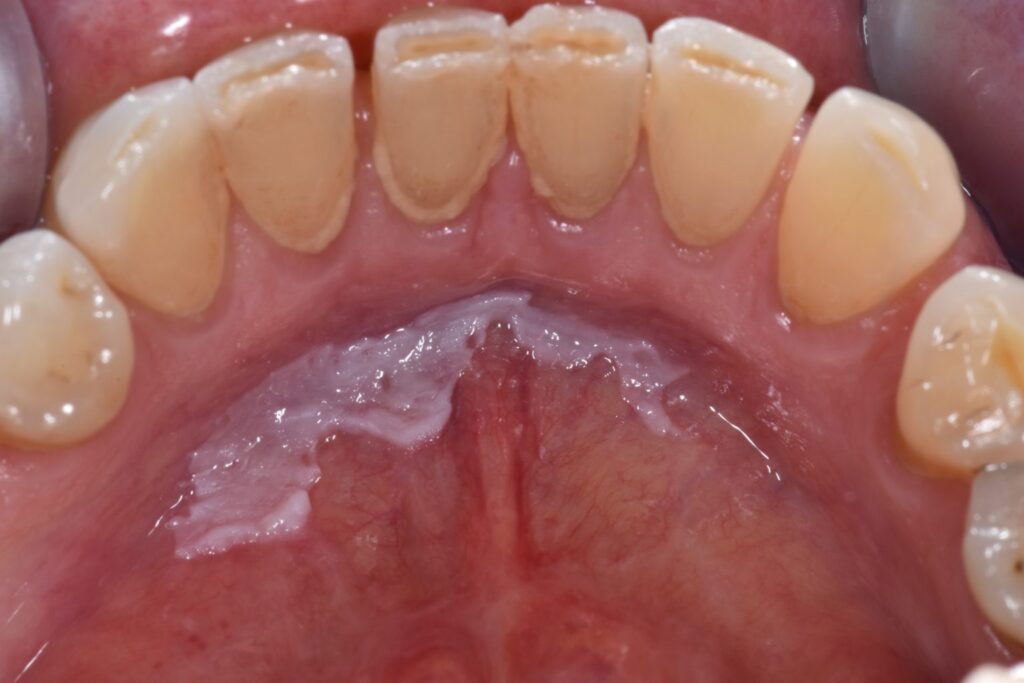

Leukoplakia jamy ustnej to biała zmiana na błonie śluzowej, której nie można usunąć poprzez potarcie i której nie da się zaklasyfikować jako innej choroby. Jest to zmiana potencjalnie przednowotworowa, dlatego wymaga szczególnej uwagi oraz diagnostyki.

Leukoplakia najczęściej objawia się jako biała plama lub płytka na błonie śluzowej.

- białe lub szarawe zmiany,

- nierówna, czasem chropowata powierzchnia,

- brak możliwości usunięcia zmiany przez potarcie,